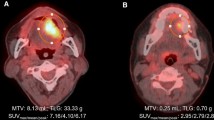

Representative cases

Figures 1 and 2 show representative cases in this study. Figure 1 shows a 51-year-old man with right tongue cancer (T4aN0M0, Stage IVA). 18F-FDG PET/CT scans showed intense accumulation of 18F-FDG (PET parameters: SUVmax, 4.2 g/ml; SUVpeak, 3.3 g/ml; MTV, 3.4 g/ml; TLG, 10.6 bw × cm3) (Fig. 1c); however, 18F-FAMT scans did not show intense accumulation (PET parameters: SUVmax, 1.7 g/ml; SUVpeak, 1.5 g/ml; MTV, 1.2 g/ml; TLR, 1.8 bw × cm3) in this patient (Fig. 1d). The patient outcomes were censored. Figure 2 shows a 63-year-old man with right tongue cancer (T2N2bM0, Stage IVA). 18F-FDG PET/CT scans showed intense accumulation of 18F-FDG (PET parameters: SUVmax, 6.4 g/ml; SUVpeak, 4.4 g/ml; MTV, 5.0 g/ml; TLG, 18.2 bw × cm3) (Fig. 2c), and 18F-FAMT scans also showed intense accumulation (PET parameters: SUVmax, 2.3 g/ml; SUVpeak, 1.8 g/ml; MTV, 6.1 g/ml; TLG, 10.5 bw × cm3) in this patient (Fig. 2d). The patient outcome was local recurrence (160 days postoperatively).